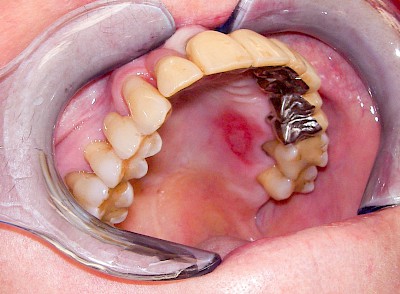

Talgdrüsen

Talgdrüsen sind wichtig für die Haut und machen diese widerstandsfähig gegen Reibungen aller Art. Die Schleimhaut jedoch braucht keine Talgdrüsen, da der Speichel die Oberfläche gut befeuchtet und damit gegen Reibung schützt. Trotzdem kommen – bei manchen Menschen durchaus sehr ausgeprägt – solche ektopen (außerörtlichen) Talgdrüsen vor. Diese haben keinen Krankheitswert und müssen nicht behandelt werden. Ektope Talgdrüsen zeigen sich häufig flächig verteilt und fallen vor allem auf im Bereich der Wangenschleimhaut oder der Lippen.